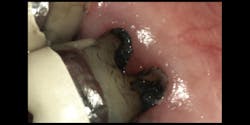

Case B: Deep decay under a crown

This patient was seen in the hygiene chair. The patient presented with deep lingual decay under the crown of tooth no. 18 (figure 1). The provider implemented hand excavation with a spoon excavator, and then the hygienist isolated the tooth and applied SDF for one minute, followed by fluoride treatment. When the patient returned to the clinic for a filling, the arrested black stained decay was removed, leaving sound structure underneath. A self-cure glass ionomer composite was placed.